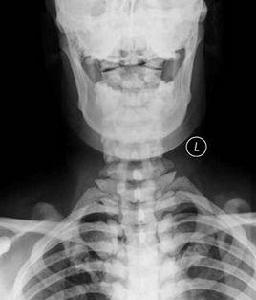

X線表現

(1)骨質疏鬆型:骨紋理粗而稀疏可為早期氟中毒性骨病的惟一表現。

(2)骨軟化症:以脊柱和骨盆明顯,其骨密度減低,紋理模糊。脊椎側彎、駝背。椎體雙凹變形。骨盆縮窄畸形和假骨折線形成。骨軟化可與骨質疏鬆,骨硬化和軟組織鈣化同時出現,呈混合型。

(3)骨硬化型:骨硬化常發生在脊柱、骨盆、肋骨和顱骨。骨紋理粗如麻袋布或礫砂狀,嚴重者骨紋理融合,結構模糊,透X線度低而似象牙。骨硬化常伴四肢骨的骨端骨質疏鬆。在顯著鈣攝入不足時可有繼發性甲旁亢,此時四肢骨呈纖維囊性骨炎表現。